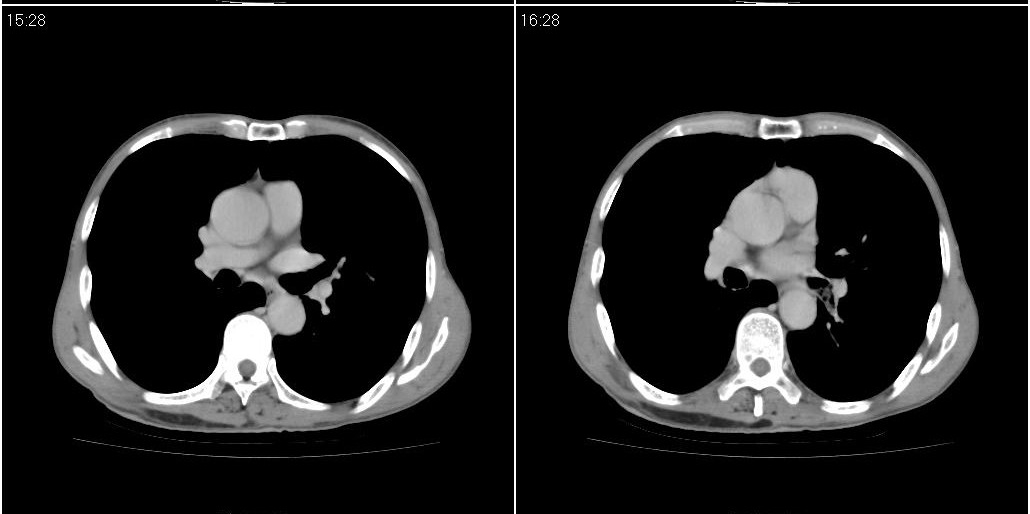

标题: ct增强:

[本贴已被 fanshl 于 2010-3-30 7:14:31 修改过]

作者: 施明 时间: 2010-3-30 16:07

炎性肿块

右肺中叶阻塞性不张及肺炎,高度怀疑支气管占位,建议纤支镜检查!